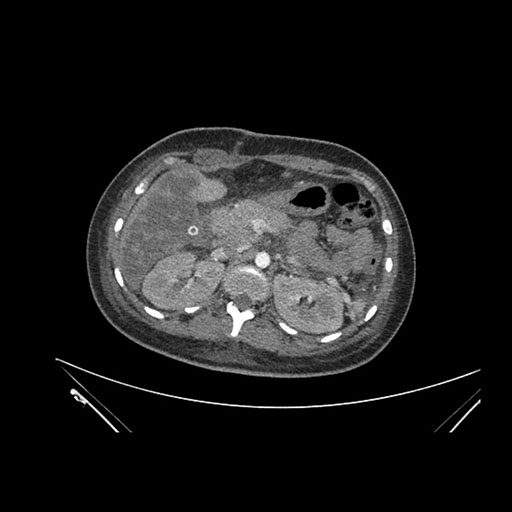

Imaging Analysis

Look through the patient's CT scan to identify any areas of concern for the necessary procedure.

Axial Venous